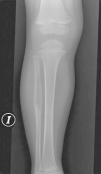

Presentamos el caso de un varón de 2 años y 11 meses, remitido a las consultas de oncohematología pediátrica y traumatología para estudio de una lesión ósea localizada en el peroné izquierdo. Tercer hijo de padres no consanguíneos, gestación a término, parto por cesárea por no evolución y en tratamiento ortopédico por pies valgos reductibles. Antecedentes familiares sin interés patológico. Quince días antes de la consulta, el niño sufre un traumatismo banal en esa pierna, presentando 48h después fiebre de 38°C axilar y deposiciones diarreicas que ceden espontáneamente. Dos días más tarde comienza con dolor en la región externa de la pierna izquierda que le impide la correcta deambulación. Durante este tiempo recibe, en régimen ambulatorio, antibioterapia con amoxicilina y claritromicina sin presentar mejoría; por lo que tras la realización de una radiografía AP y lateral de la pierna izquierda, en la que se objetiva una lesión lítica localizada en la diáfisis del peroné izquierdo de aproximadamente 6cm, que rompe la cortical y con reacción perióstica (fig. 1), es remitido a nuestro hospital. En la exploración física destaca una tumefacción en la región externa de la pierna izquierda sin otros signos locales de inflamación (no calor ni rubor), dolor a la palpación en dicha localización, sin heridas aparentes y cojera al apoyar el miembro afectado. Con los datos clínicos y las características radiológicas de agresividad de la lesión ósea, se solicitan diferentes exámenes complementarios en los que destacan una hemoglobina de 11,4g/dl con microcitosis, hipocromía discreta y anisocitosis, 8.700/μl leucocitos (neutrófilos 4.900/μl; linfocitos 2.650/μl), PCR normal (3mg/l), VSG de 32mm/h, perfil bioquímico incluida lactato deshidrogenasa y ferritina, inmunoglobulinas, complemento y coagulación normales, y serologías (virus de Epstein-Barr, citomegalovirus y parvovirus) negativas. La resonancia magnética confirma la lesión de la diáfisis del peroné izquierdo de 10 x 1,5 x 2cm, que expande y rompe la cortical, con importante reacción perióstica, muy sugestiva de lesión agresiva, con pequeña cantidad de edema/afectación de partes blandas, y que capta contraste tras la administración de gadolinio (fig. 2). El diagnóstico diferencial radiológico baraja la posibilidad de un sarcoma de Ewing (SE) versus osteomielitis, y considerar osteosarcoma o granuloma eosinófilo (GEo), como otras posibilidades más remotas. La gammagrafía ósea con 99Tc pone de manifiesto la lesión ósea en la mitad superior diafisaria del peroné izquierdo, con incremento de vascularización, sin observar otras captaciones patológicas, y no descarta ninguno de los diagnósticos referidos. Ante todos estos hallazgos, se realiza una biopsia de la lesión por punción (trucut), informada como tejido reactivo/reparativo en posible relación con una fractura previa. El cultivo de esta y el estudio molecular de SE resultaron negativos. Dada la disociación clínico-radiológica e histológica, se decide realizar una biopsia abierta, que confirma el diagnóstico definitivo de GEo. Tras la confirmación diagnóstica, se adopta una actitud expectante, objetivándose una evolución clínica y radiológica del todo favorable.